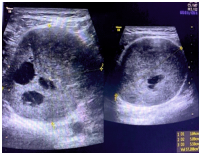

Ultrasound scan (USG) of the soft tissue using a 7-9 MHz transducer (Voluson S Pro 8 GE) of the left leg was performed which showed a 5.5 × 5.0 × 3.5 cm in the posterior aspect of the lower left thigh. The lesion was solid, homogenously hypoechoic and without any calcification. There were a few small cystic changes noted within the lesion (Figure 2). The lesion showed that arterial as well as venous flow and the lesion were separate from the surrounding bone and muscle (Figure 3). The sciatic nerve passed through the lesion.

Figure 2: USG of the left thigh